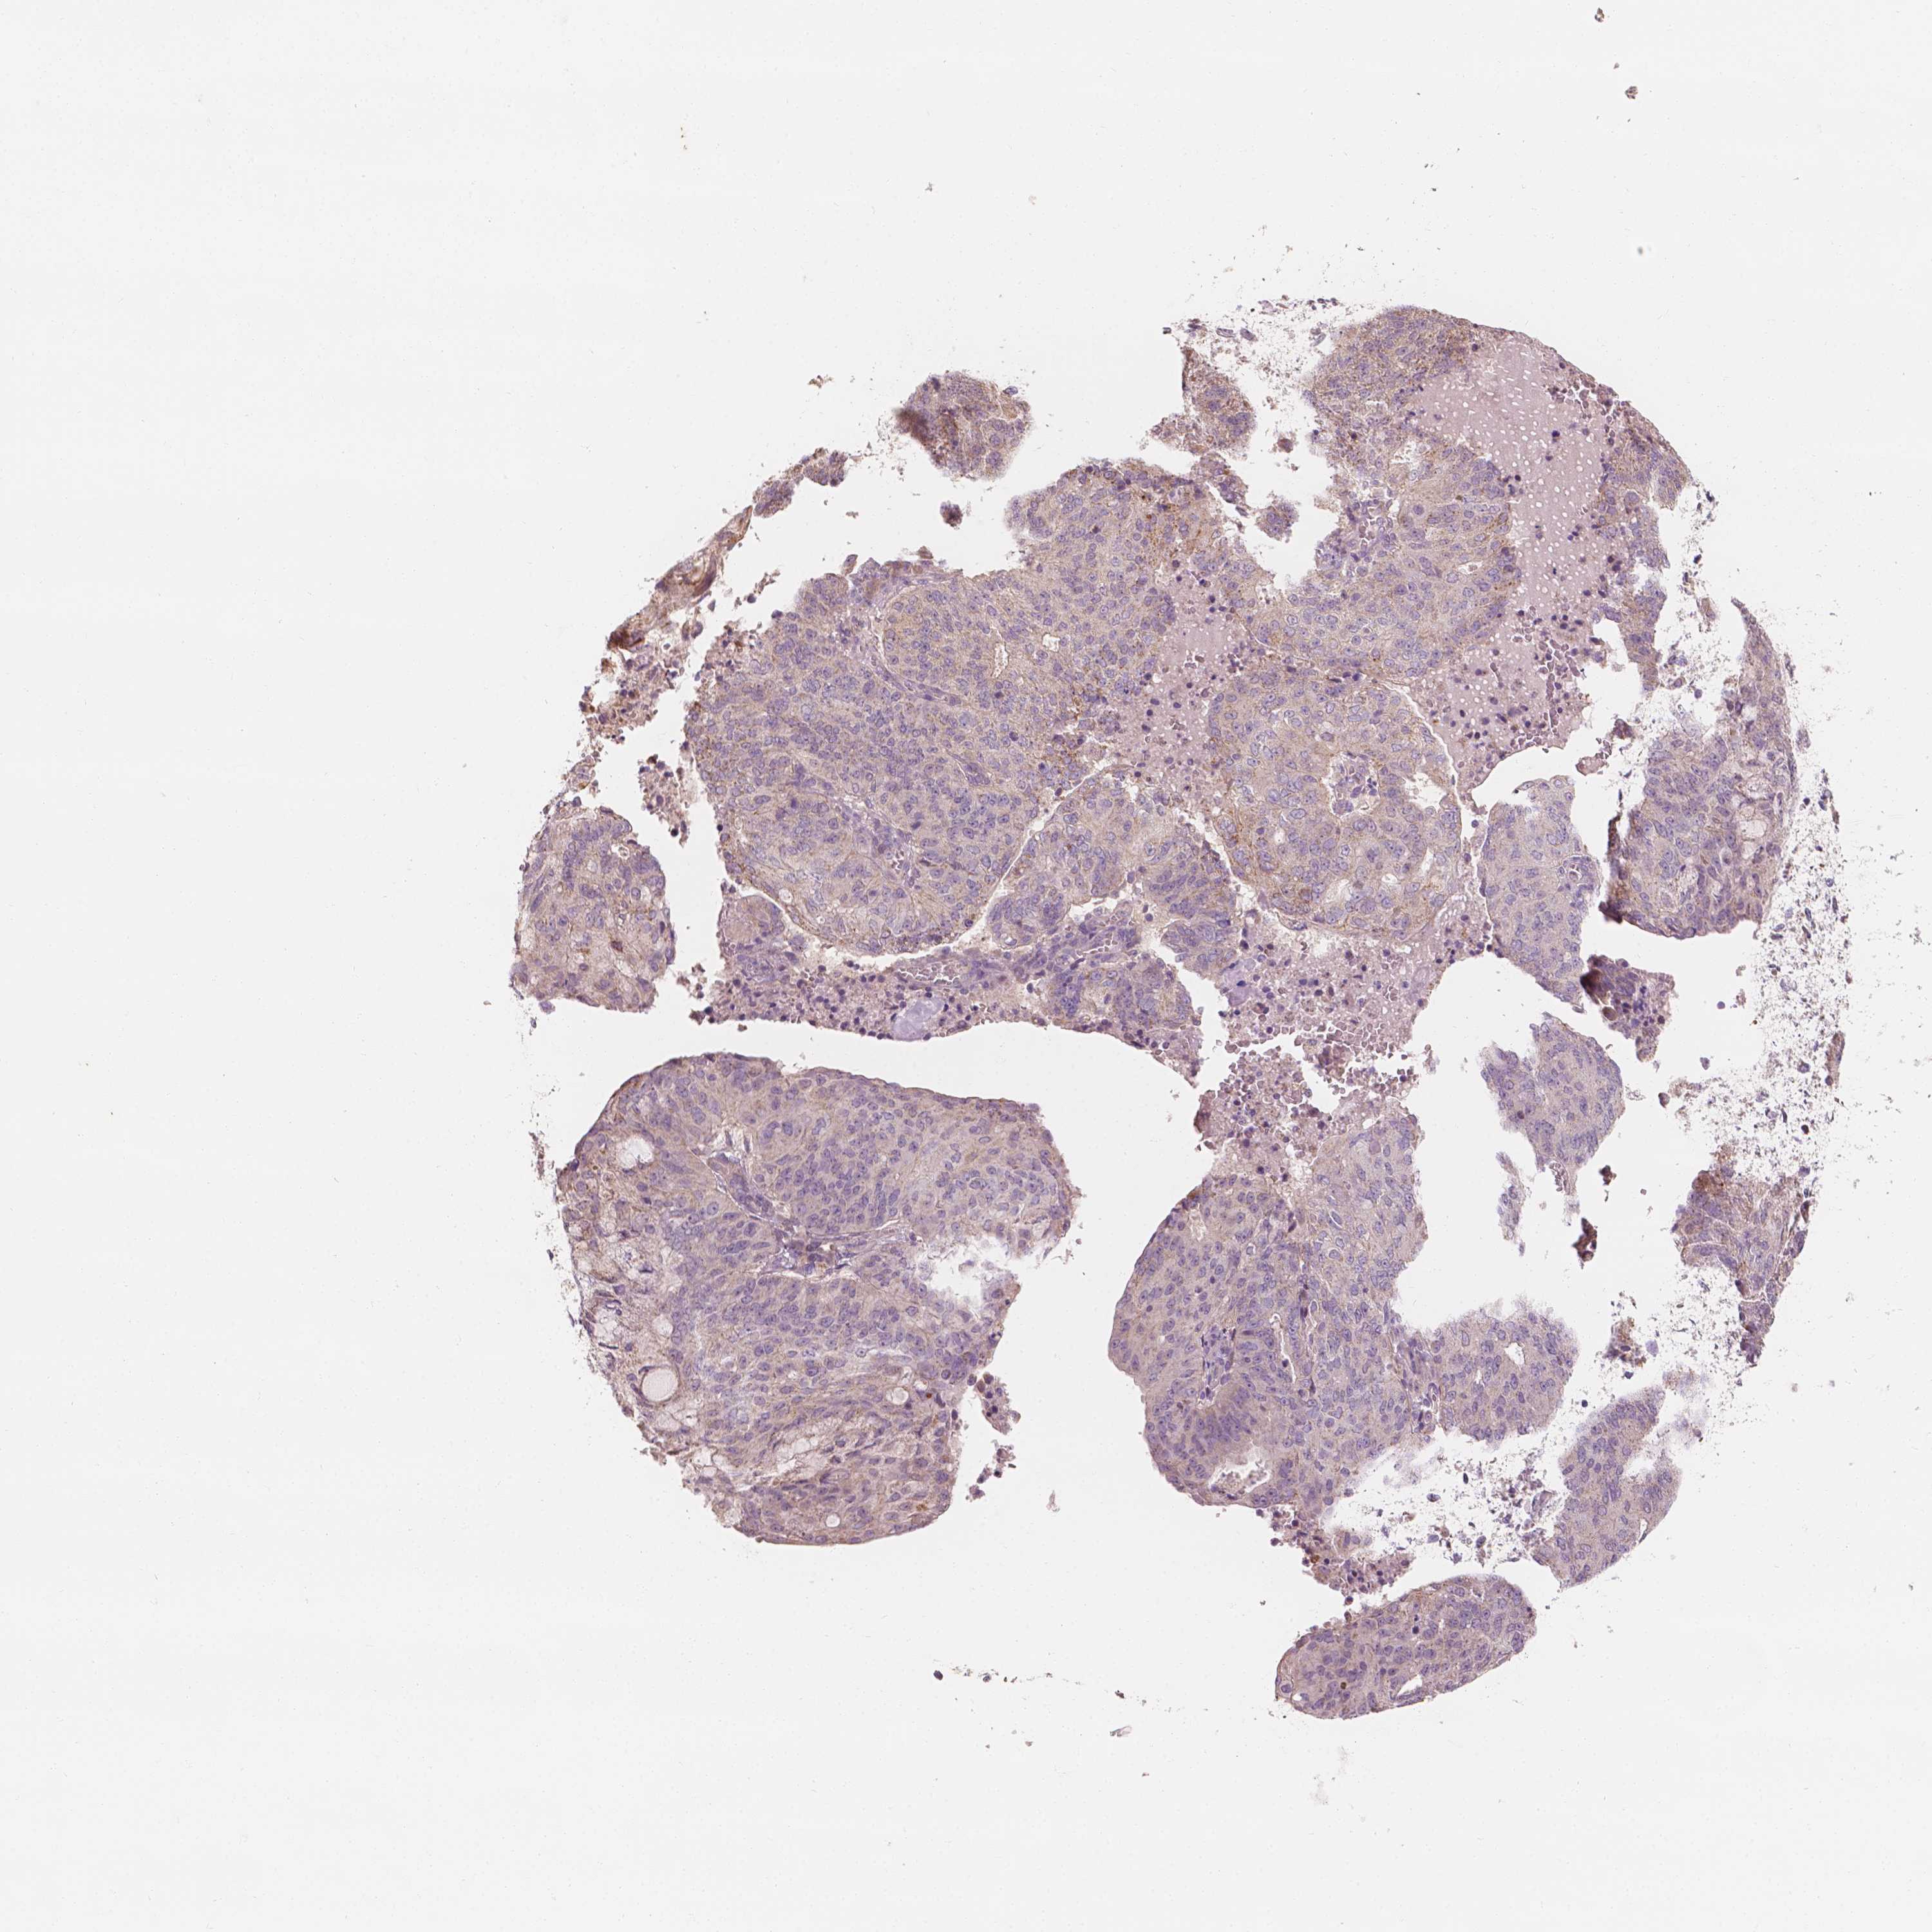

ENDOMETRIAL CANCER - Protein expressioni

A mouse-over function shows sample information and annotation data. Click on an image to view it in a full screen mode. Samples can be filtered based on level of antibody staining by selecting one or several of the following categories: high, medium, low and not detected. The assay and annotation is described here.

Note that samples used for immunohistochemistry by the Human Protein Atlas do not correspond to samples in the TCGA dataset.

Antibody stainingi

Antibody staining in the annotated cell types in the current human tissue is reported as not detected, low, medium, or high, based on conventional immunohistochemistry profiling in selected tissues. This score is based on the combination of the staining intensity and fraction of stained cells.

Each image is clickable and will lead to virtual microscopy that enables deeper exploration of all samples and also displays staining intensity scores, fraction scores and subcellular localization as well as patient and tissue information for each sample.

Antibody HPA024361

Antibody HPA064939

Staining

High

Medium

Low

Not detected

Intensity

Strong

Moderate

Weak

Negative

Quantity

>75%

75%-25%

<25%

None

Location

Nuclear

Cytoplasmic/membranous

Cytoplasmic/membranous,nuclear

Adenocarcinoma, NOS

Carcinoma, NOS